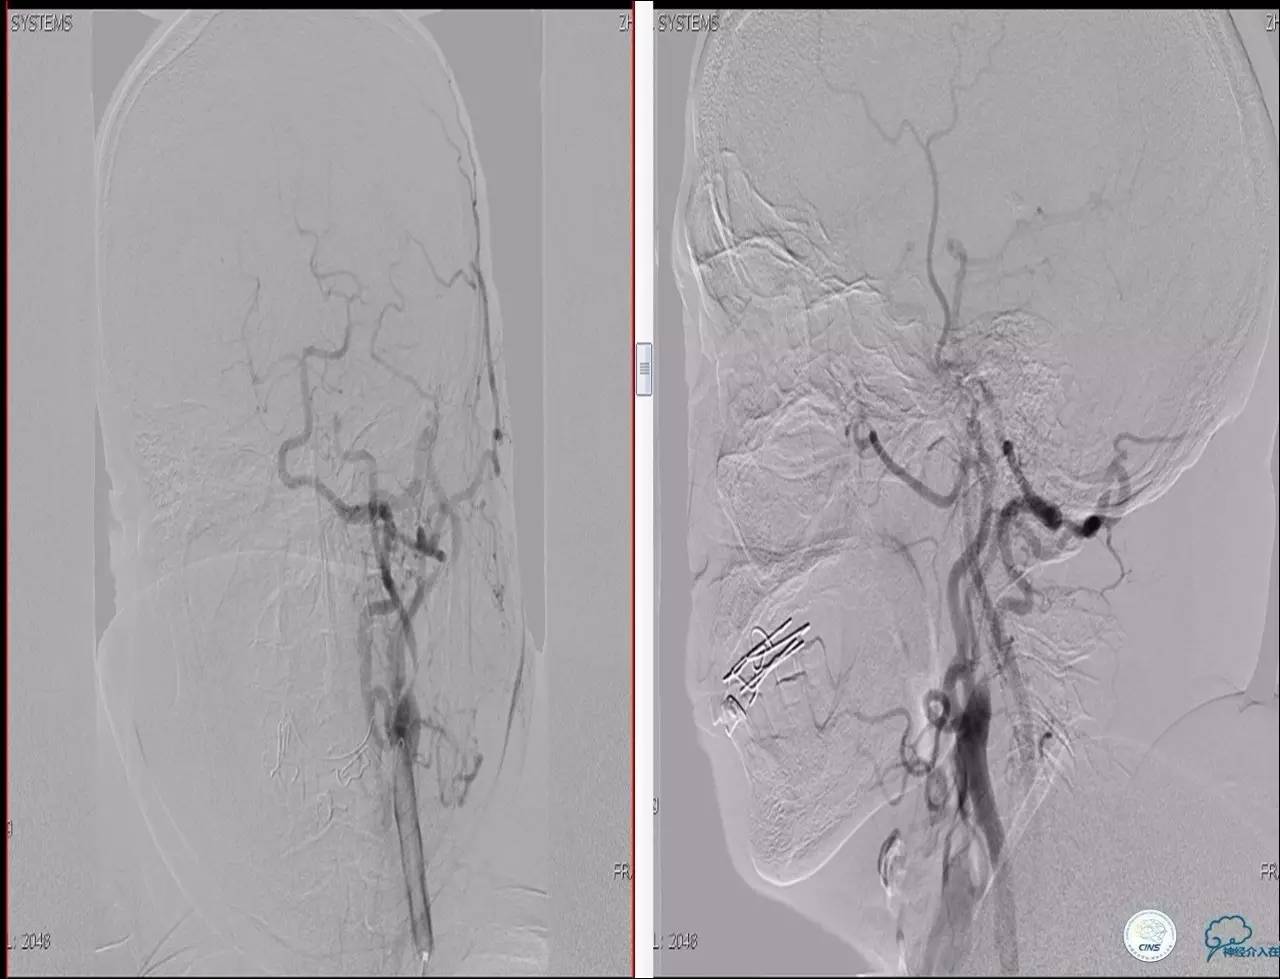

Case 1

》男,70岁。

》主诉:阵发性头晕伴视物模糊两月余。

》查体:右侧肌力V-级。

》既往史:高血压,糖尿病。

》辅助检查:颈动脉B超显示:左侧颈内动脉起始部狭窄 90%,右侧颈内动脉起始部80%。